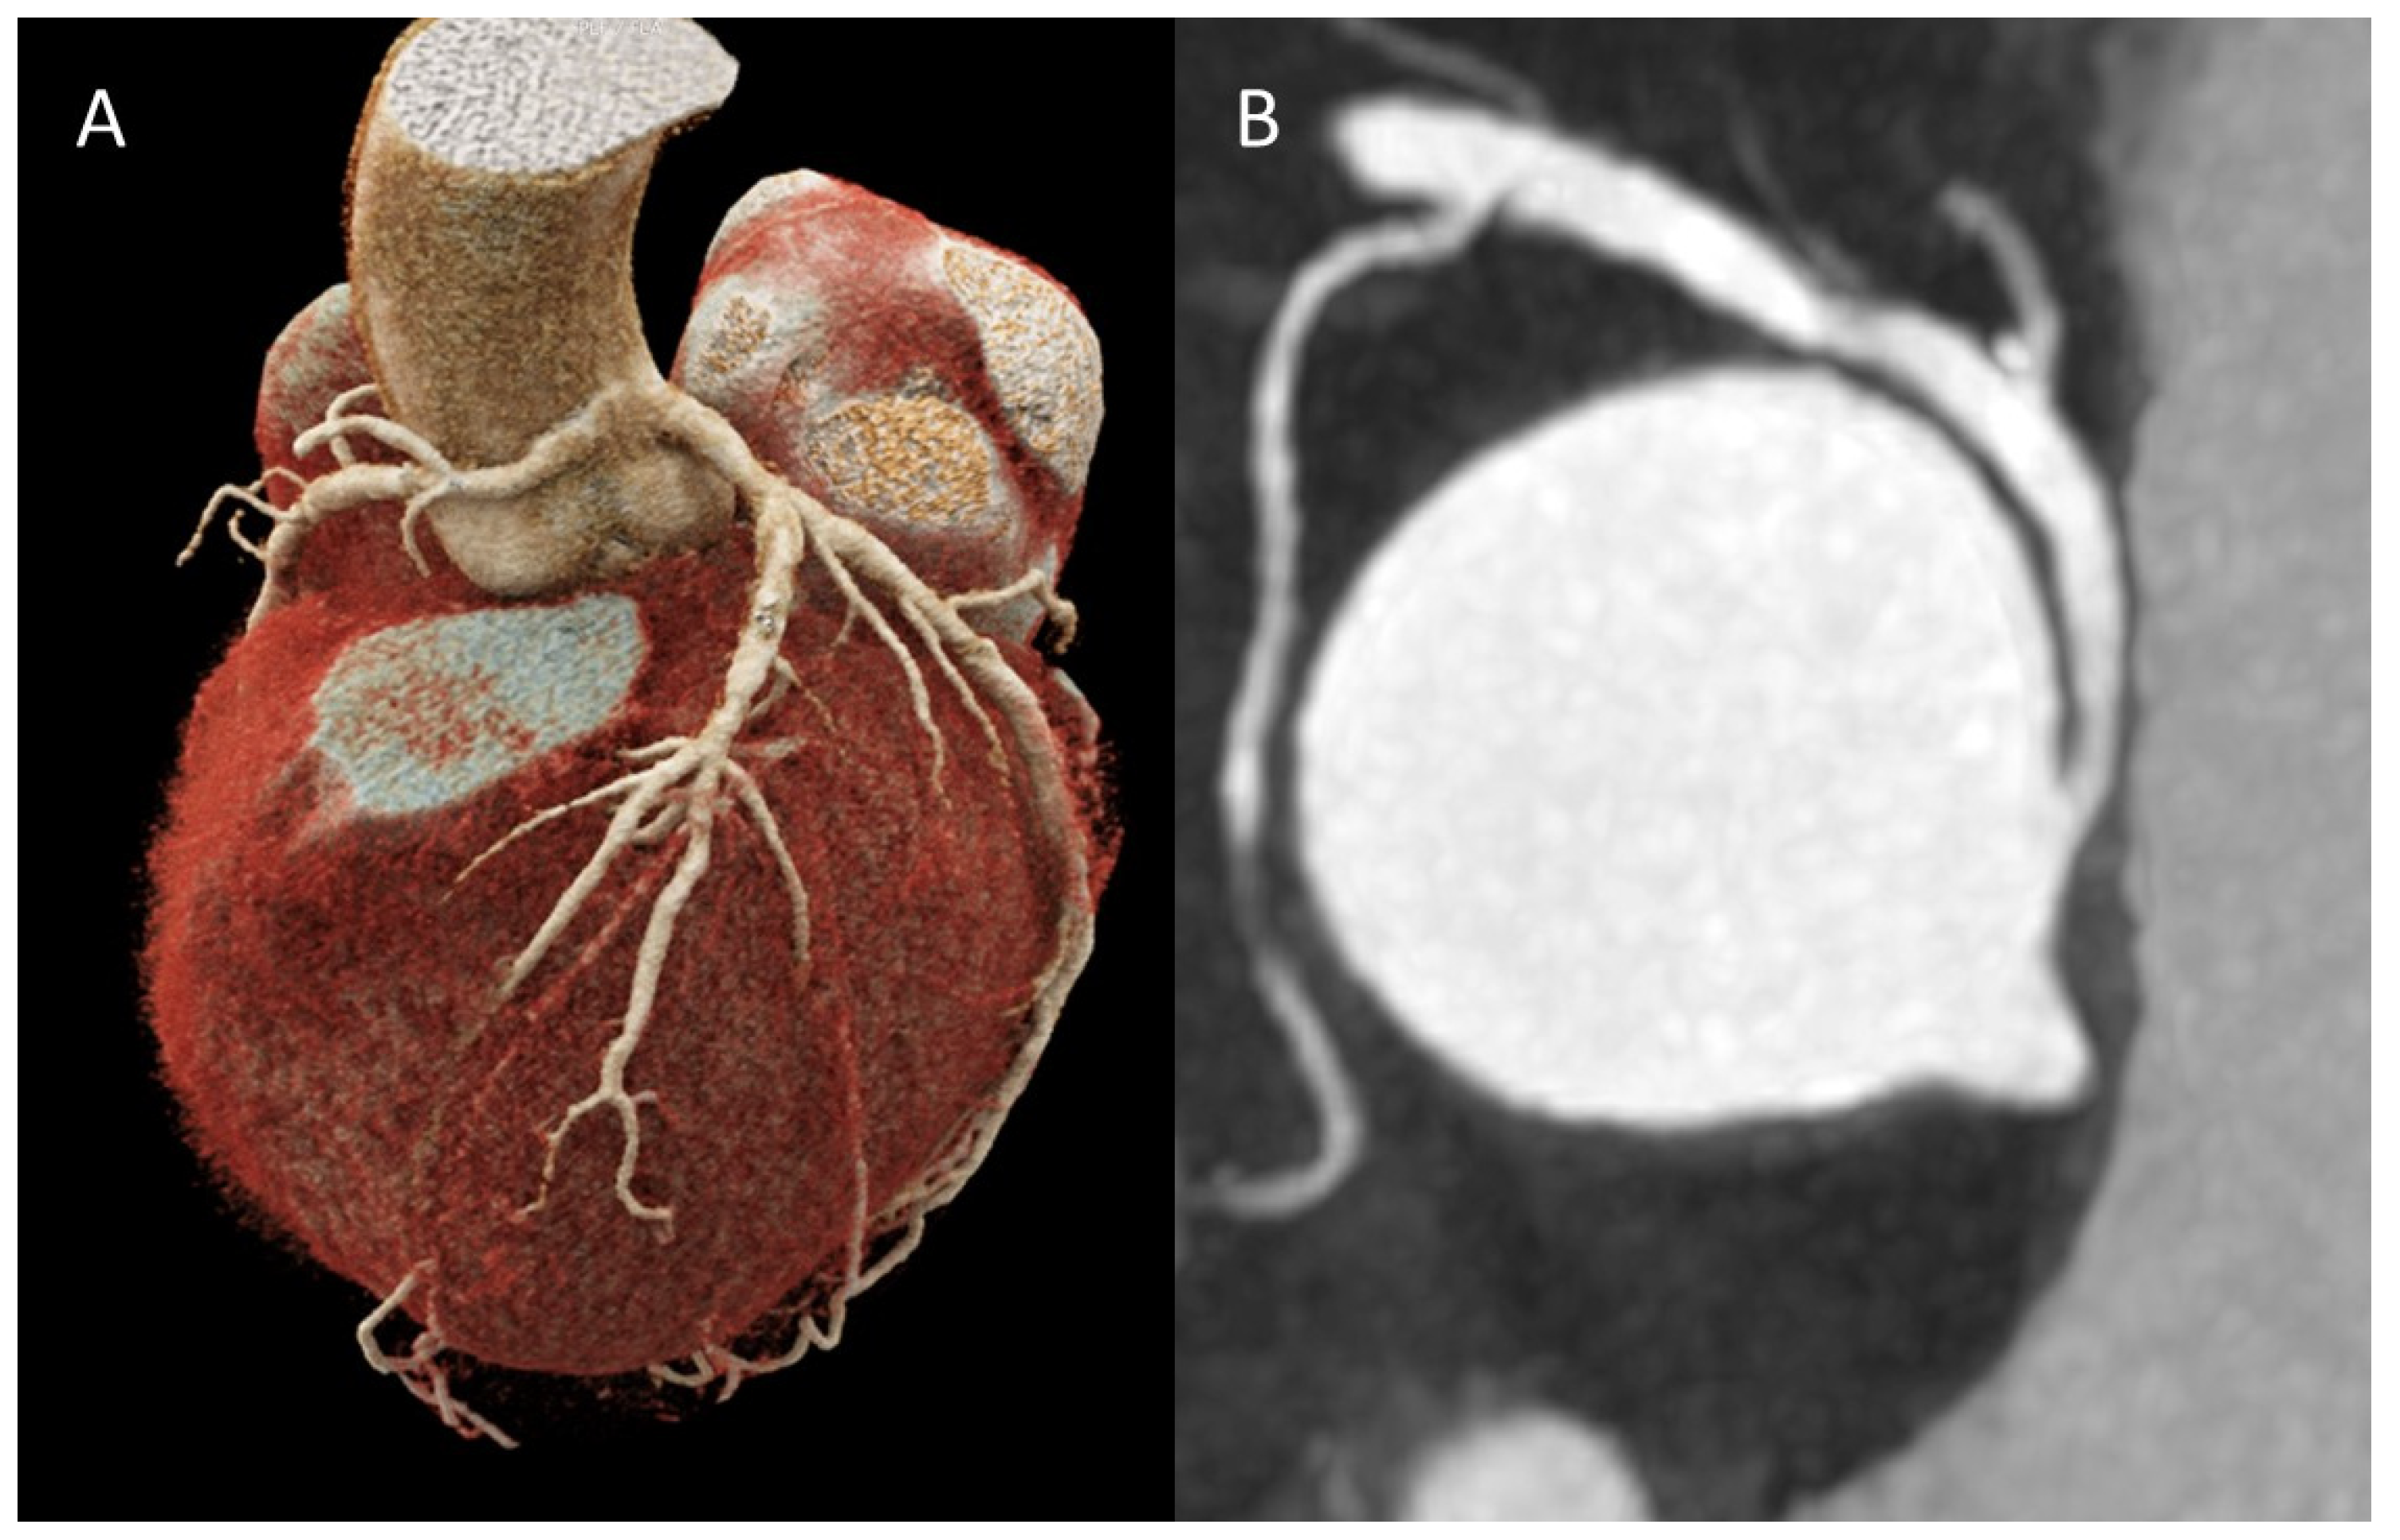

Figure 2. (A) Three-dimensional representation of an absent left main trunk or congenital atresia of the left main trunk. (B) CCTA image showing an absent left main trunk.

4.1.1. Congenital Atresia of the Left Main Trunk

This anomaly is a rare condition and has two different types of presentation: LCX and LAD can each have an independent origin, which is anatomical variant, and has a prevalence of 0.41% to 0.67% with no clinical consequence or it can be a much rarer but serious form, left main trunk hypoplasia, characterized by the absence of a true left main trunk. Collateral vessels are then formed between the coronary arteries; however, they are usually insufficient to adequately perfuse the LV and therefore leading to myocardial ischemia, in most cases, during the first year of life (Class II Rigatelli) (14,16). (Figure 2).